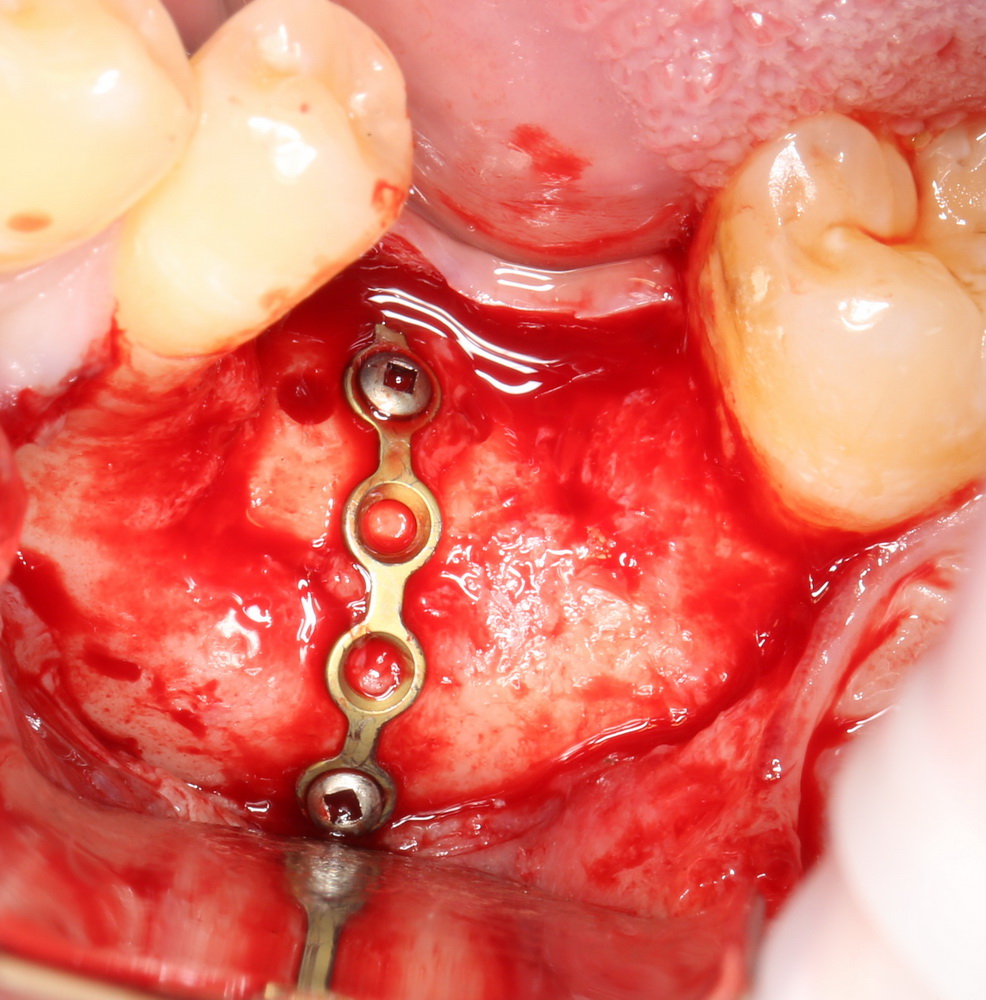

Начну с того, что BioGide — это лучшее, что есть сейчас на рынке, а остальные мембраны ей завидуют. Как и в случае с макродизайном имплантов, именно физические свойства определяют как удобство использования, так и возможность достижения нужного результата. Прочность, эластичность, легкая адаптация и адгезия делают ненужными использование фиксирующих пинов. Мы просто закрываем мембраной графт — и все, можно накладывать швы:

В другом ракурсе видно, какой объем тканей мы восстанавливаем:

и теперь швы. Наглухо (Фактор II):